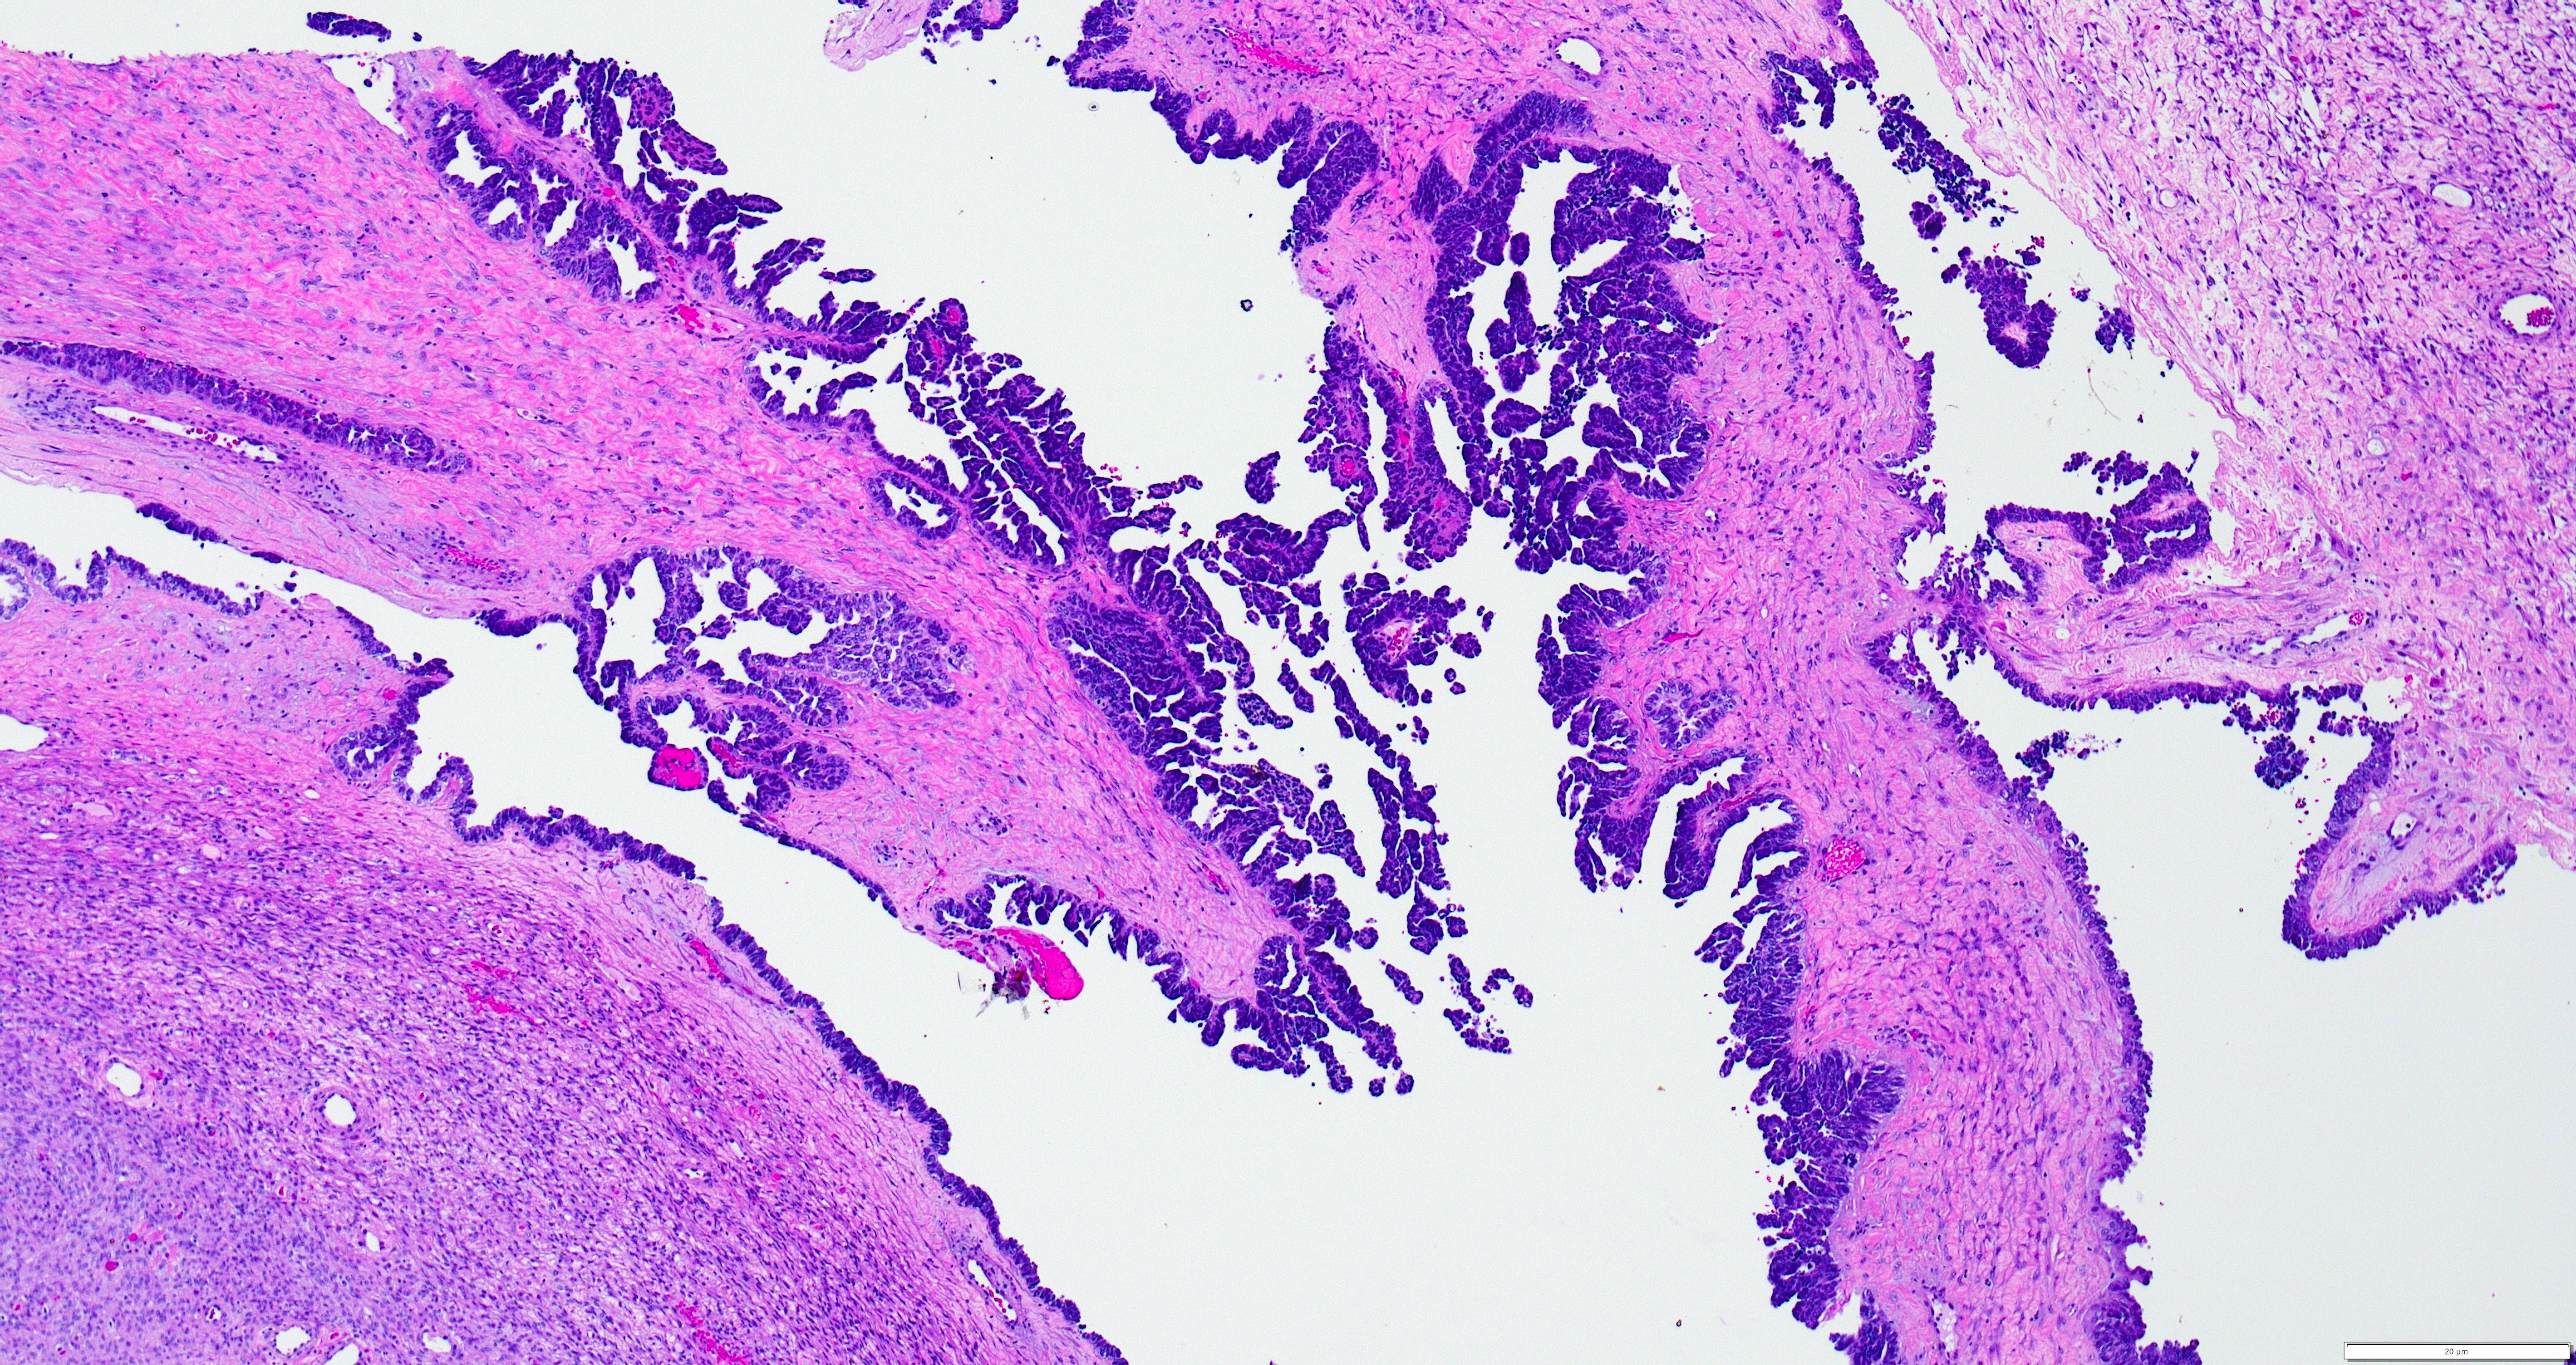

- Variety of histologic patterns that may be present within the same tumor

- Most frequently small tubules with ductal / glandular growth

- Papillary, solid growth, trabecular, retiform, sex cord-like, sieve-like, glomeruloid and spindle cell areas have all been described

- Luminal eosinophilic secretions are characteristic but not always identified

- Tumor cells can be flattened, cuboidal or columnar with mild to moderate cytological atypia

- Clear cell features can be seen but are less common

- High grade cytological atypia is usually not a predominant feature

- Nuclei show vesicular chromatin and nuclear grooves

- Sarcomatoid transformation has been seen in rare instances

- Squamous, ciliated or mucinous differentiation (metaplasia) are not present and there are no associated mesonephric remnants (J Clin Med 2021;10:698)

Microscopic (histologic) images

Contributed by Daniel Graham, M.D., Adele Wong, M.B., B.Ch., B.A.O. and Lucy Ma, M.D.